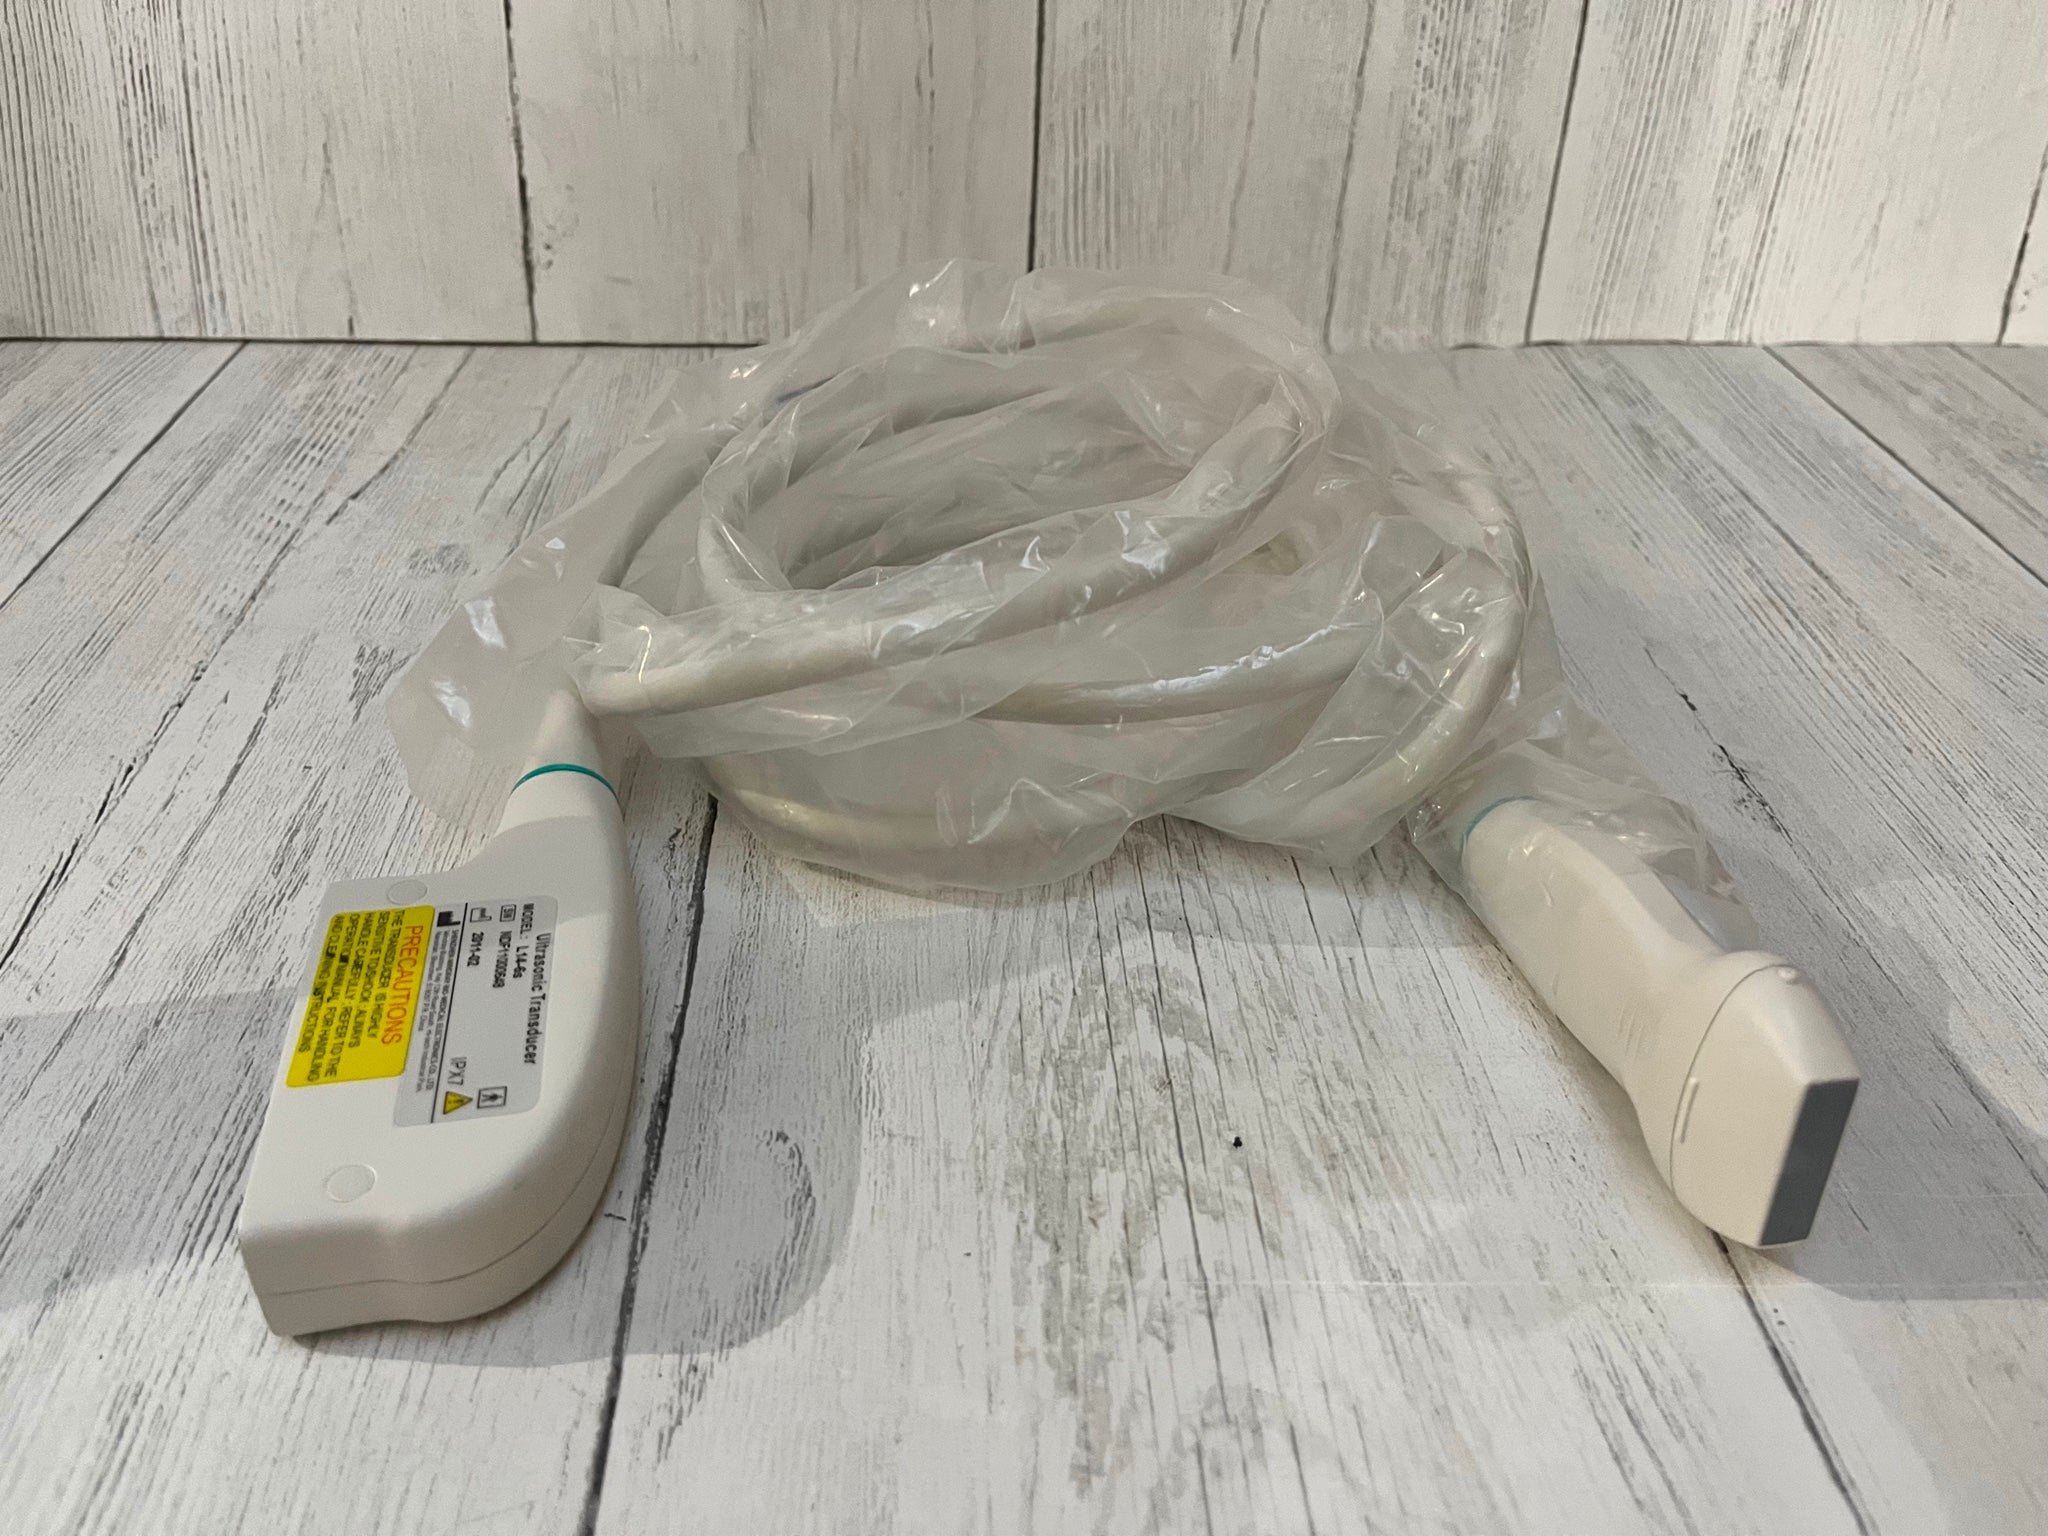

Probe is in good condition no compatible ultrasound to test the item. For the power cord, if you see a separate picture of the power cord, you'll receive it. Otherwise, we used the power cord only to test the item.